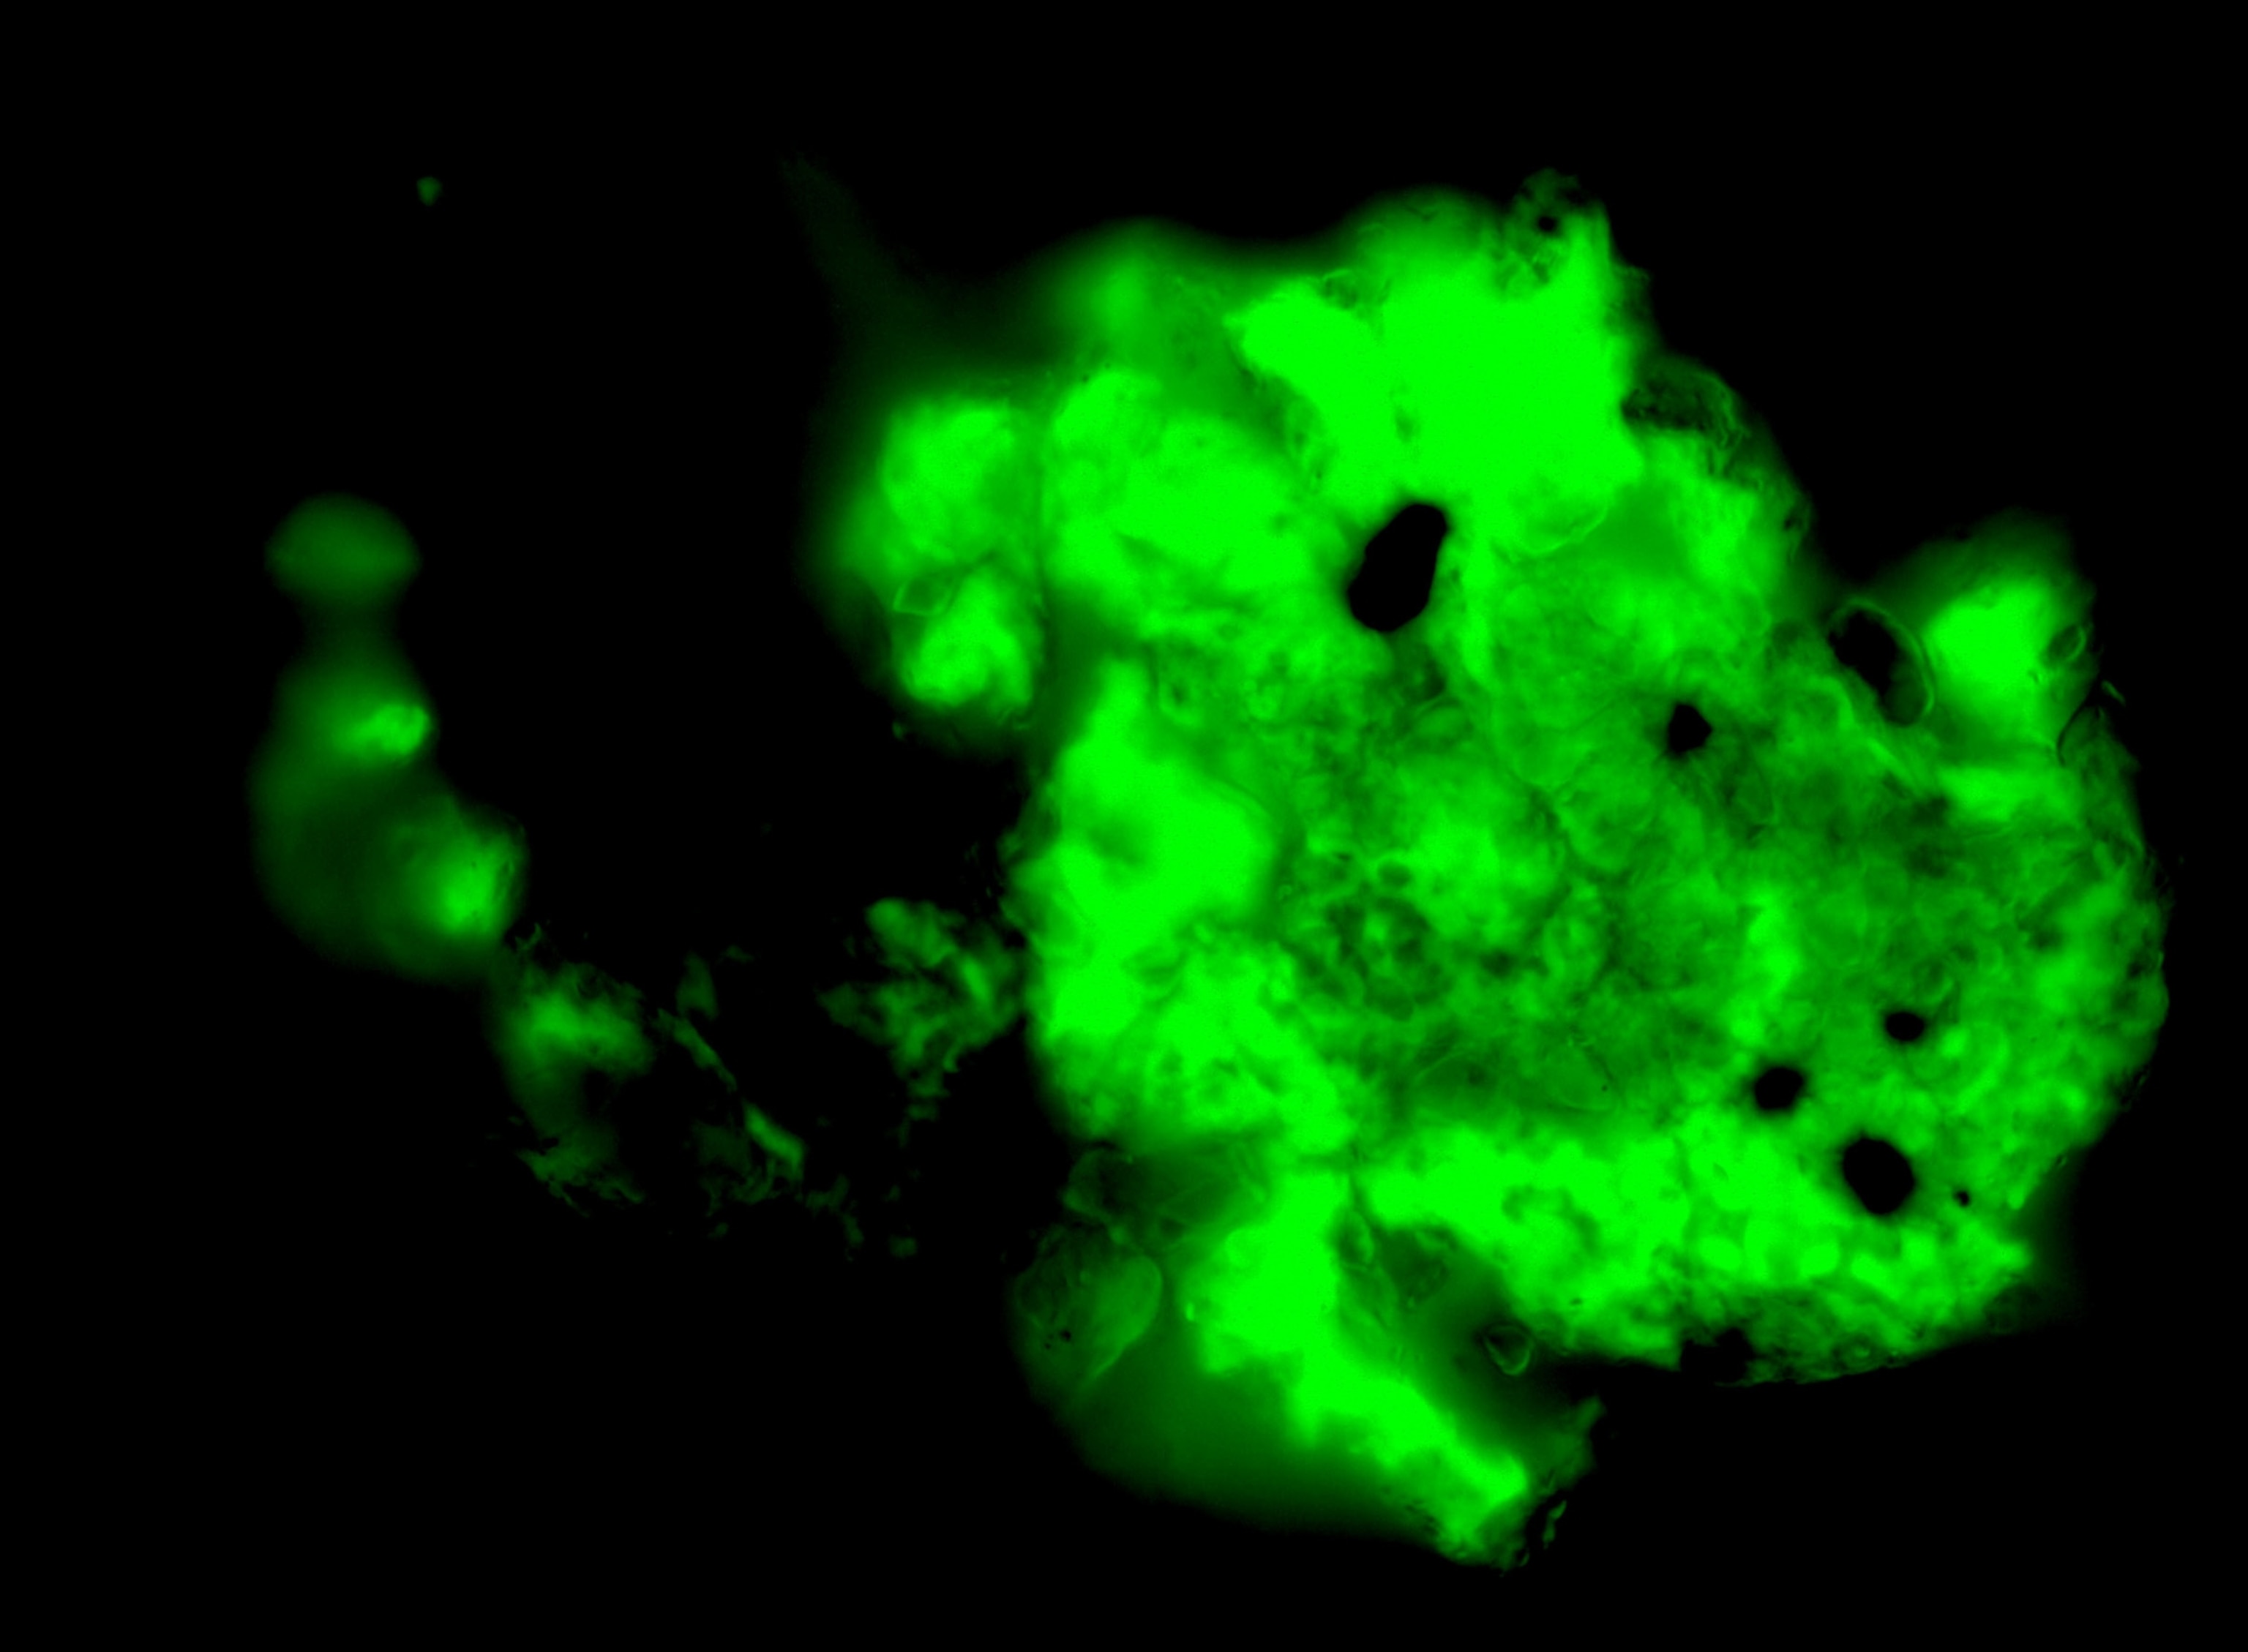

When she first saw the microscope images of fluorescent green blobs revealing the microclots, she cried with relief. For her, the confirmation that she has microclots felt like validation of her illness, “especially after not getting a PCR test at the beginning and being gaslit throughout the last few years.”

Detecting microclots requires a specialized laboratory technique called fluorescence microscopy. “You can’t just go to the doctor’s office and get tested for microclots,” says microbiologist Amy Proal, of the nonprofit PolyBio Research Foundation and co-founder of the long COVID Research Initiative.

The process involves drawing blood, spinning it, and adding a fluorescent agent to see the clots under a fluorescence microscope. It’s not a widely available tool in general pathology labs.

For now, Putrino and his team are seeing a correlation between the number of microclots on a microscope slide and the severity of a patient’s cognitive impairment. These include their ability to regulate emotions, plan and put together long-term solutions to problems, or figure out ways to deal with real-time situations as they’re changing. The research team is also developing an objective measure for microclots. “We’re still at a very rudimentary stage,” Putrino says.